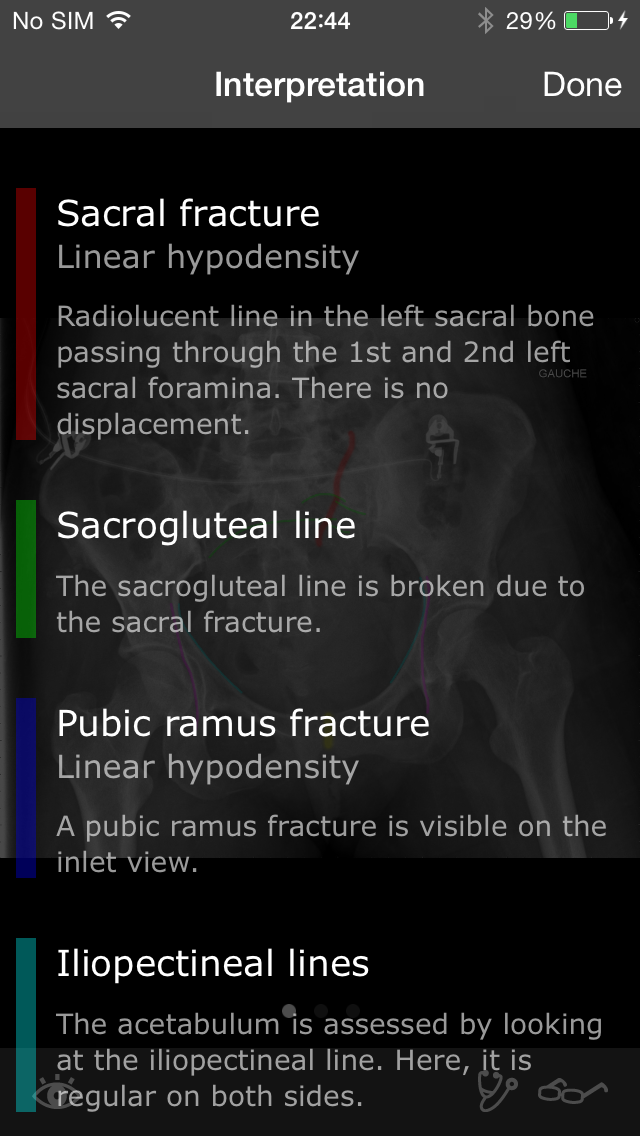

Скриншоты